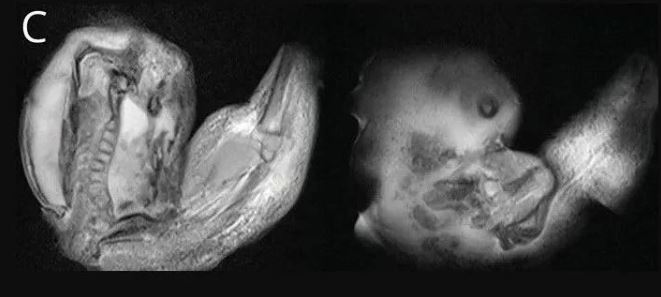

İleri incelemeler, bebeğin aslında anne karnındayken bir ikiz kardeşi olduğunu ama ikinci bebeğin yeterince gelişemeyerek kardeşinin kafatasının içine sıkıştığını ortaya çıkardı.

Doğmamış ikiz kardeşin, doktorların deyimiyle "fetiform kitlenin" üst uzuvları ve hatta parmak benzeri çıkıntıları bile gelişmiş gibi görünüyordu.

Ancak fetüsün gövdesi ve diğer kısımları yeterince gelişememişti.

Sonuçta yeterince gelişemeyen bu embriyo diğeri tarafından içerilmişti. Böylece gelişmemiş olan bebek, diğerinin kafatasına sıkışmıştı.